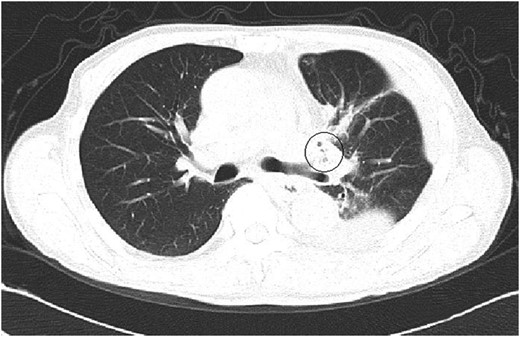

A 61-year-old male underwent a left upper lobectomy in January 2014. The lobar bronchus was cut and closed with a suturing device. A pedicled intercostal muscle flap or pericardial fat tissue was not used to cover the bronchial stump because there were no risk factors for broncho-pleural fistula (BPF) such as diabetes. The patient's postsurgical course was not particularly eventful. He was dismissed 8 days after surgery but was re-admitted a week later due to excessive retention of pleural fluid on the operated side. The computed tomography (CT) scan images showed nothing remarkable other than a few tiny air spaces around the bronchial stump (Fig. 1). The patient complained of an obstinate dry cough that had not improved since his operation. He was discharged 11 days after his second admission, after successful control of pleural fluid. Neither microorganisms nor cancer cells were present in the fluid.

A CT image at the second admission. A few small bubbles could be seen in the pleural space adjacent to the left upper bronchial stump. No major thoracic air space was observed.